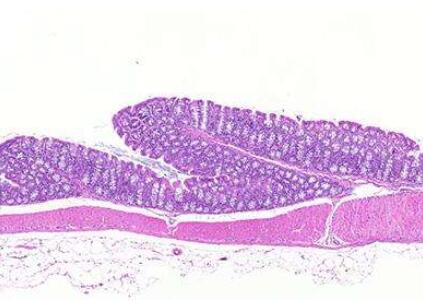

为了鉴定出这些突变,这些研究人员使用激光捕获显微镜(laser capture microscopy)从捐赠的组织样本中切出了单个“隐窝(crypt)”,这些隐窝一起构成了结肠组织。隐窝内的每个细胞都有相同的基因突变。他们研究了来自42名年龄在11至78岁之间的人的总共2035个隐窝。他们开发出一种新的工作流程对激光捕获的隐窝进行基因组测序。他们随后让能够对成千上万个基因组进行快速测序的过程实现了完全自动化。